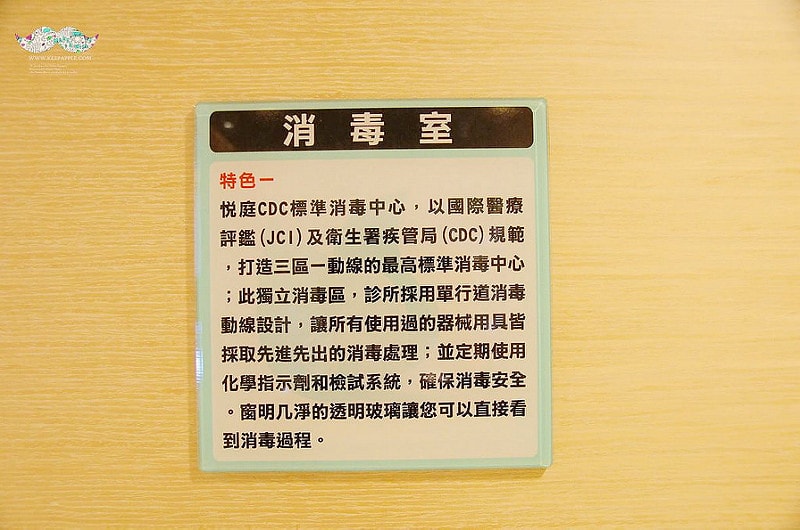

還有專屬三區一動線的消毒室(髒汙區、清潔區、消毒區)

一般消毒過了四級才算安全的消毒

在悅庭的標準則是第六級化學指示劑監測

完全就是跟大醫院相同等級的超高規格呢!

打包好的器械由這張檯面輸送進行高消喔

病患們可以更放心